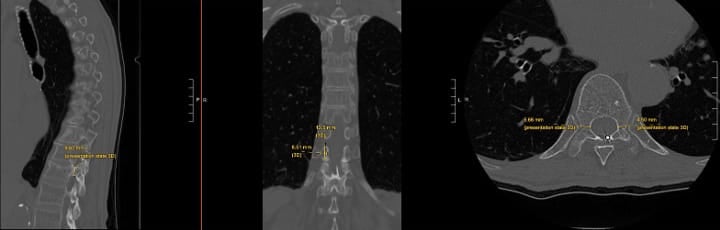

Off-Label Treatment Above L3

While FDA approval covers the L3-S1 levels, select cases may warrant treatment of higher levels with modic changes and a high level of confidence that the motion segment is a source of pain. Treatment above L3 requires exceptional care due to the progressively smaller pedicles and proximity of the neural structures (Figures 3 and 4).

Critical considerations include (1) mandatory pedicle diameter measurement, (2) CT scan for pre-procedure planning is strongly recommended, (3) modified trajectory angles (ie parapedicular or extrapedicular approaches) to accommodate anatomy, (4) increased vigilance for neural structure proximity, and (5) potential for vascular trespass if an extrapedicular approach is being considered (segmental arteries).